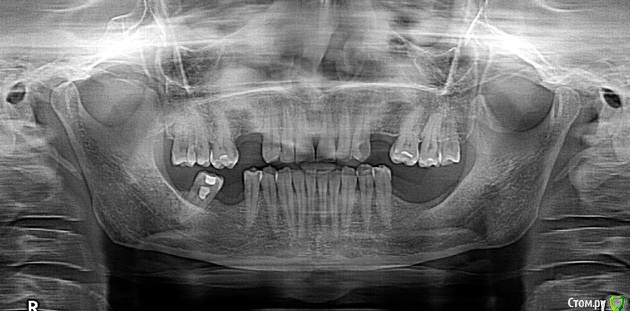

Barbar Опубликовано 24 июня, 2018 Поделиться Опубликовано 24 июня, 2018 Добрый вечер всем! Пожалуйста, помогите принять правильное решение по имплантатам, чтобы на долгие годы не заморачиваться темой зубы.Шлю актуальный рентгеновский снимок. Посетила трёх имплатологов и у всех разные решения.1. Врач: в верхней челюсти по 2 импланта на каждой стороне, в нижней - 3. Без наращивания кости.2. Врач: в верхней челюсти по 2 импланта на каждой стороне, в нижней - 3. С наращиванием кости в нижней челюсти.3. Врач: в верхней челюсти на каждой стороне по 1 импланту с дополнительной как бы "висящей в пространстве" коронкой, в нижней - 3 импланта, как и у других. Без наращивания кости.Что посоветуете, если учесть, что размер дыры между зубами в верхней челюсти 11 и 10 мм?Спасибо за помощь! Ссылка на комментарий